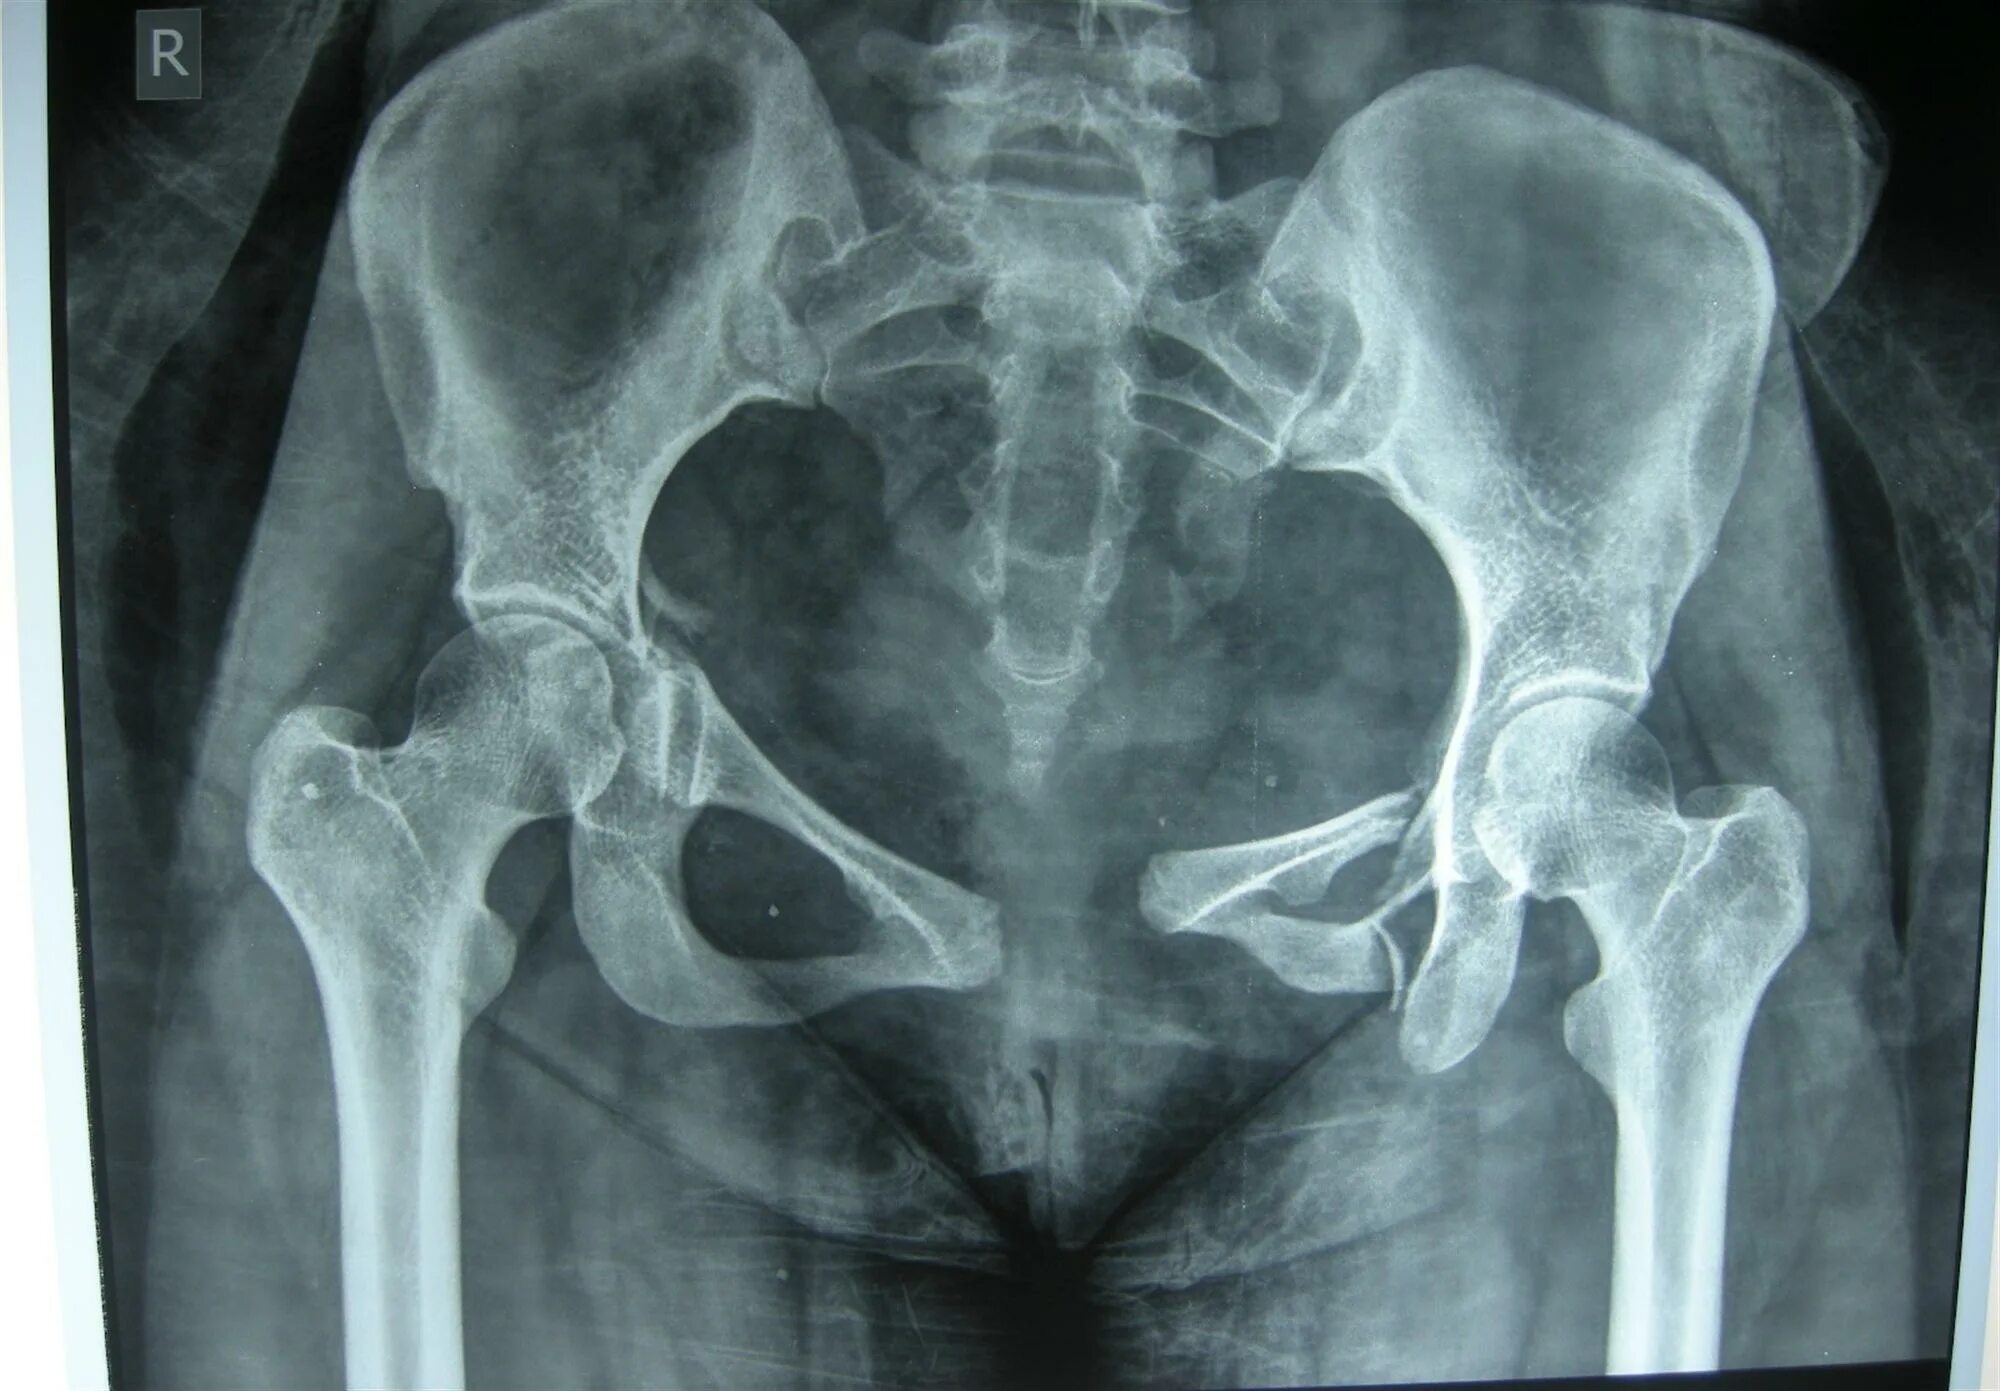

Source x rays